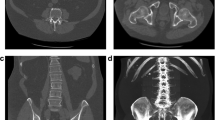

Assessment of Genant scores from CT scans is challenging even for an experienced radiologist because CT scans provide 3D geometry and spatial resolution is lower than for spinal X-rays. Topics to consider are: (1) should coronal or sagittal CT reformations (or both) be used for spinal fracture assessment? (2) The use of single slices may easily result in overlooking fractures (Fig. 2) but how many slices should be averaged? In the case of scoliosis (coronal reformations) or kyphosis (sagittal reformations), the central slice of the set to be averaged may depend on vertebral level (Fig. 2). Also in contrast to X-rays, there is no atlas or extended description for CT to differentiate osteoporotic from traumatic fractures and from vertebral deformities unrelated to osteoporosis [41].

Left: coronal and sagittal reformations of CT dataset of the spine; top: simulated X-rays; center: original CT reformations; bottom: 10 slices averaged. Right: subject with sclerosis demonstrating that different coronal planes must be reconstructed from a CT dataset in order to assess mid-sagittal planes

Another perspective is the use of dual-energy CT that originally has been introduced for the reduction of the so-called fat error of single-energy CT [92,93,94]. Whether DECT could also benefit the accuracy of internal calibration still has to be investigated, first studies showed promising results [71, 77, 95, 96]. Also, the reduction of BMD inaccuracies caused by the administration of contrast agents should be a topic of future research. A further step will be the use of photon-counting CT scanners that will boost the use of CT in many areas because of several new features. One of the most important ones is the further reduction of radiation exposure. Figure 6 shows some very early results obtained on a prototype photon-counting device using excised vertebral bodies [97]. In this study radiation exposure was reduced by a factor of two without any degradation of image quality. Another important feature of photon counting CT is the further decomposition of the spectral response beyond the capabilities of DECT.

Dose reduction of photon counting CT using an excised vertebral body. Single energy CT: 120 kV, 355 mAs, 23.8 mGy, Photon counting 120 kV, 130 mAs, 10.5 mGy. The image noise (σ) is identical in both scans with a reduction of radiation exposure by more than 2 in the case of photon counting. For both scans, comparable high-resolution kernels were used [97]